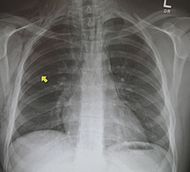

肋骨骨折の患者様レントゲンです。

脇腹の痛みを訴えての来院です。骨折の疑いがある場合は、提携医療機関を

ご紹介します。